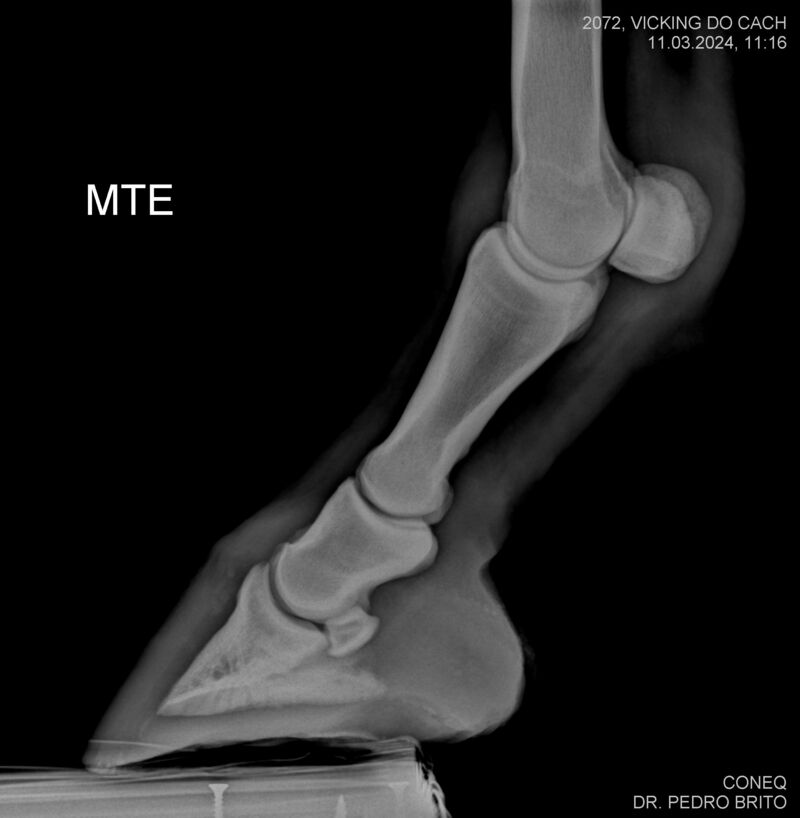

VIKING DO CACH